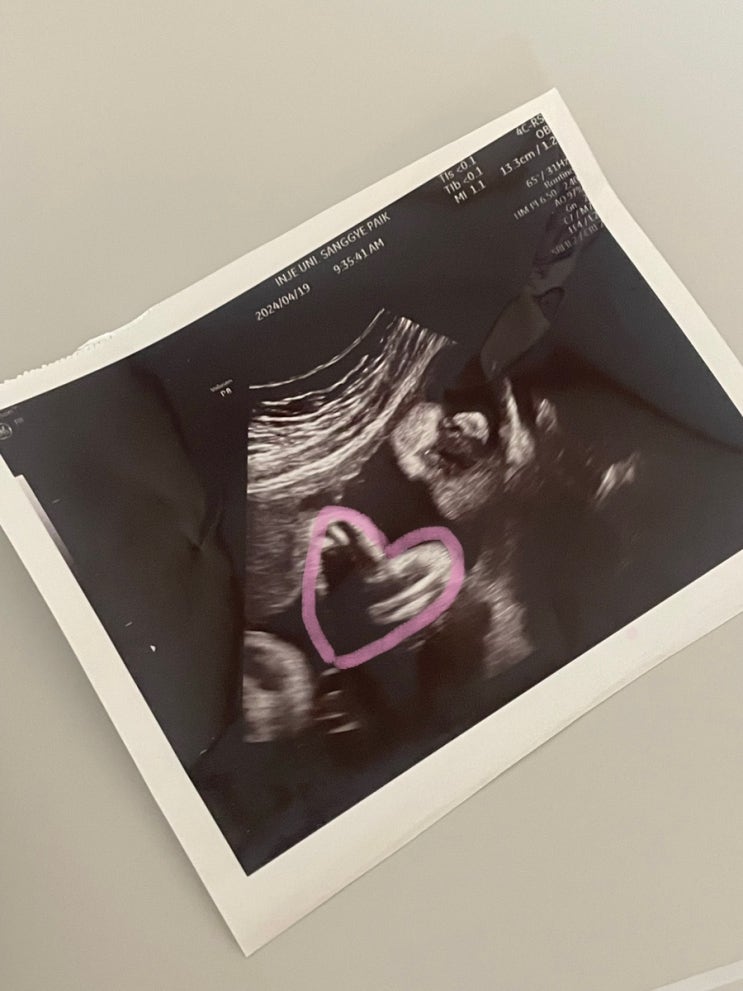

27w1d~27w3d - 포천공공산후조리원 실패 and 퇴원실패 후 27주된 하품하는 방울이

2024.04.01 4월 1일이라 원래 계획대로라면 포천공공산후조라원 티켓팅을 하기위해 pc방에 있을텐데.... 갑...